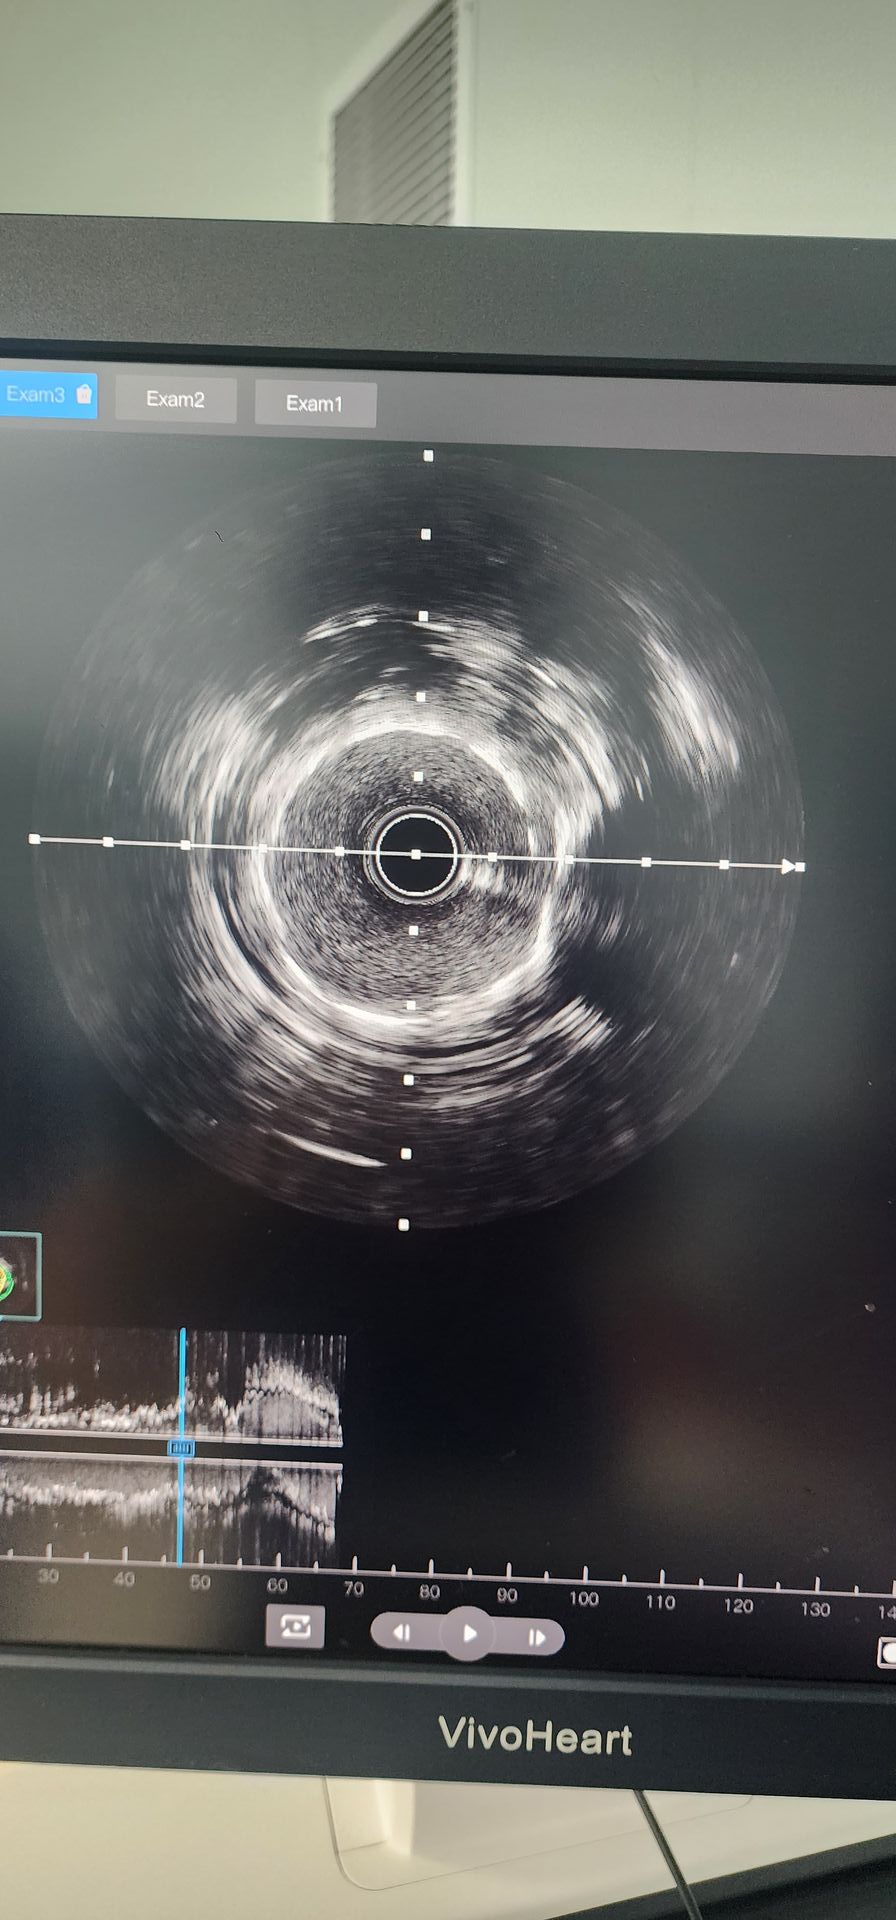

Коронарная ангиография выявила тяжелую кальцификацию с 95% стенозом в проксимальной окружной артерии и 85%-90% кальцинированным стенозом в средней правой коронарной артерии.

Проксимальная циркумфлексная артерия: начальная предварительная дилатация баллоном 2,0 × 20 показала плохие результаты. Затем был использован катетер расширения воздушного шара 2,5 × 12 Lepu Vesscrack Coronary IVL, обеспечивающий четыре цикла, успешно разрушая кальцинированное поражение. После значительного улучшения стеноза стент 2,5 × 14 был успешно имплантирован, с удовлетворительными ангиографическими результатами.

Средняя правая коронарная артерия: начальное пре-дилатация баллоном 2,5 × 20 привела к ограниченному улучшению. Затем катетер с расширенным баллоном 2,5 × 12 Lepu Vesscrack Coronary IVL использовался в течение двух циклов, что значительно улучшило стеноз в кальцинированной области. Затем был успешно имплантирован стент 3,0 × 19, что дало удовлетворительные ангиографические результаты.